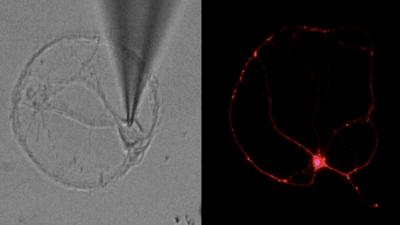

In their study, conducted in animal models as well as brain cells derived from human stem cells, Lipton and his team mapped the pathway that leads to synaptic damage in Alzheimer's. They found that amyloid beta peptides, which were once thought to injure synapses directly, actually induce the release of excessive amounts of the neurotransmitter glutamate from brain cells called astrocytes that are located adjacent to the nerve cells.

Normal levels of glutamate promote memory and learning, but excessive levels are harmful. In patients suffering from Alzheimer's disease, excessive glutamate activates extrasynaptic receptors, designated eNMDA receptors (NMDA stands for N-methyl-D-aspartate), which get hyperactivated and in turn lead to synaptic loss.

By shutting down hyperactive eNMDA receptors on diseased neurons, NitroMemantine restores synapses between those neurons. "We show in this paper that memantine's ability to protect synapses is limited," Lipton said, "but NitroMemantine brings the number of synapses all the way back to normal within a few months of treatment in mouse models of Alzheimer's disease. In fact, the new drug really starts to work within hours."